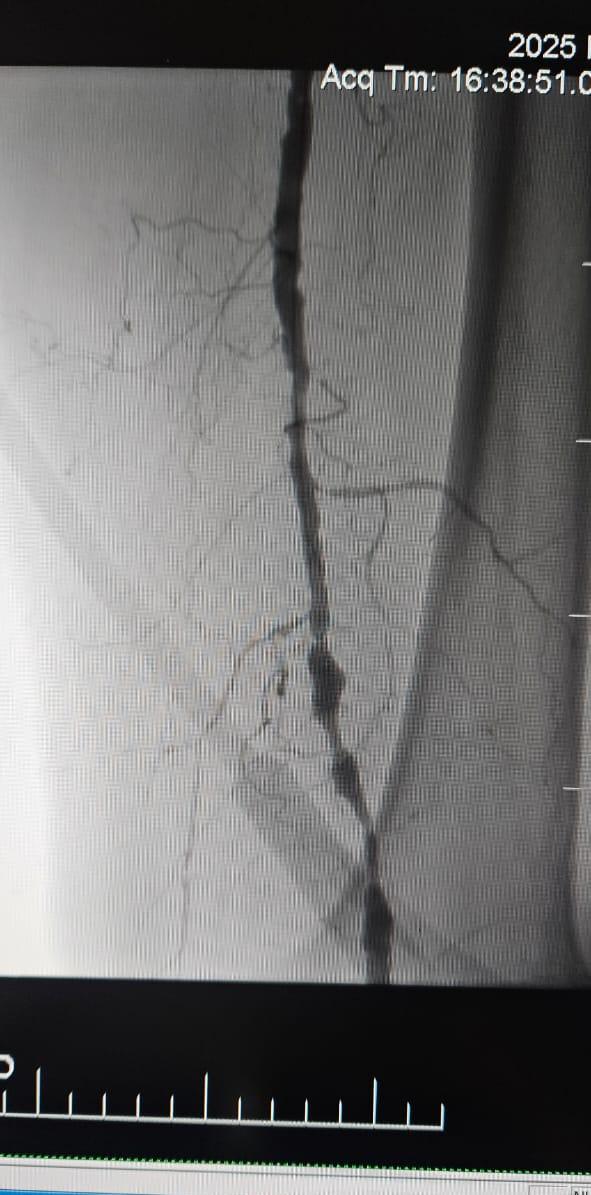

Klinischer Fall im Rampenlicht: Chronische CLI-Okklusion mit ThorCrack-IVL behandelt

Wir freuen uns, einen erfolgreichen Fall aus einem Krankenhaus in Batumi, Georgia, zu teilen, in dem eine 78-jährige Patientin mit kritischer Extremitäten ischämie (CLI), die durch einen chronischen vollständigen Verschluss der Arterie der unteren Extremitäten verursacht wurde, nach der Behandlung mit dem ThorCrack Peripheral IVL Balloon Dilatation Catheter System.

Dieser Fall unter streicht den klinischen Wert der intra vaskulären Litho tripsie (IVL) bei der Behandlung komplexer CLI-Fälle mit chronischer Okklusion mit langem Segment-insbesondere bei Patienten mit starker Verkalkung, bei denen herkömmliche Ballons oder Atherektomie geräte möglicher weise eine begrenzte Wirksamkeit aufweisen.